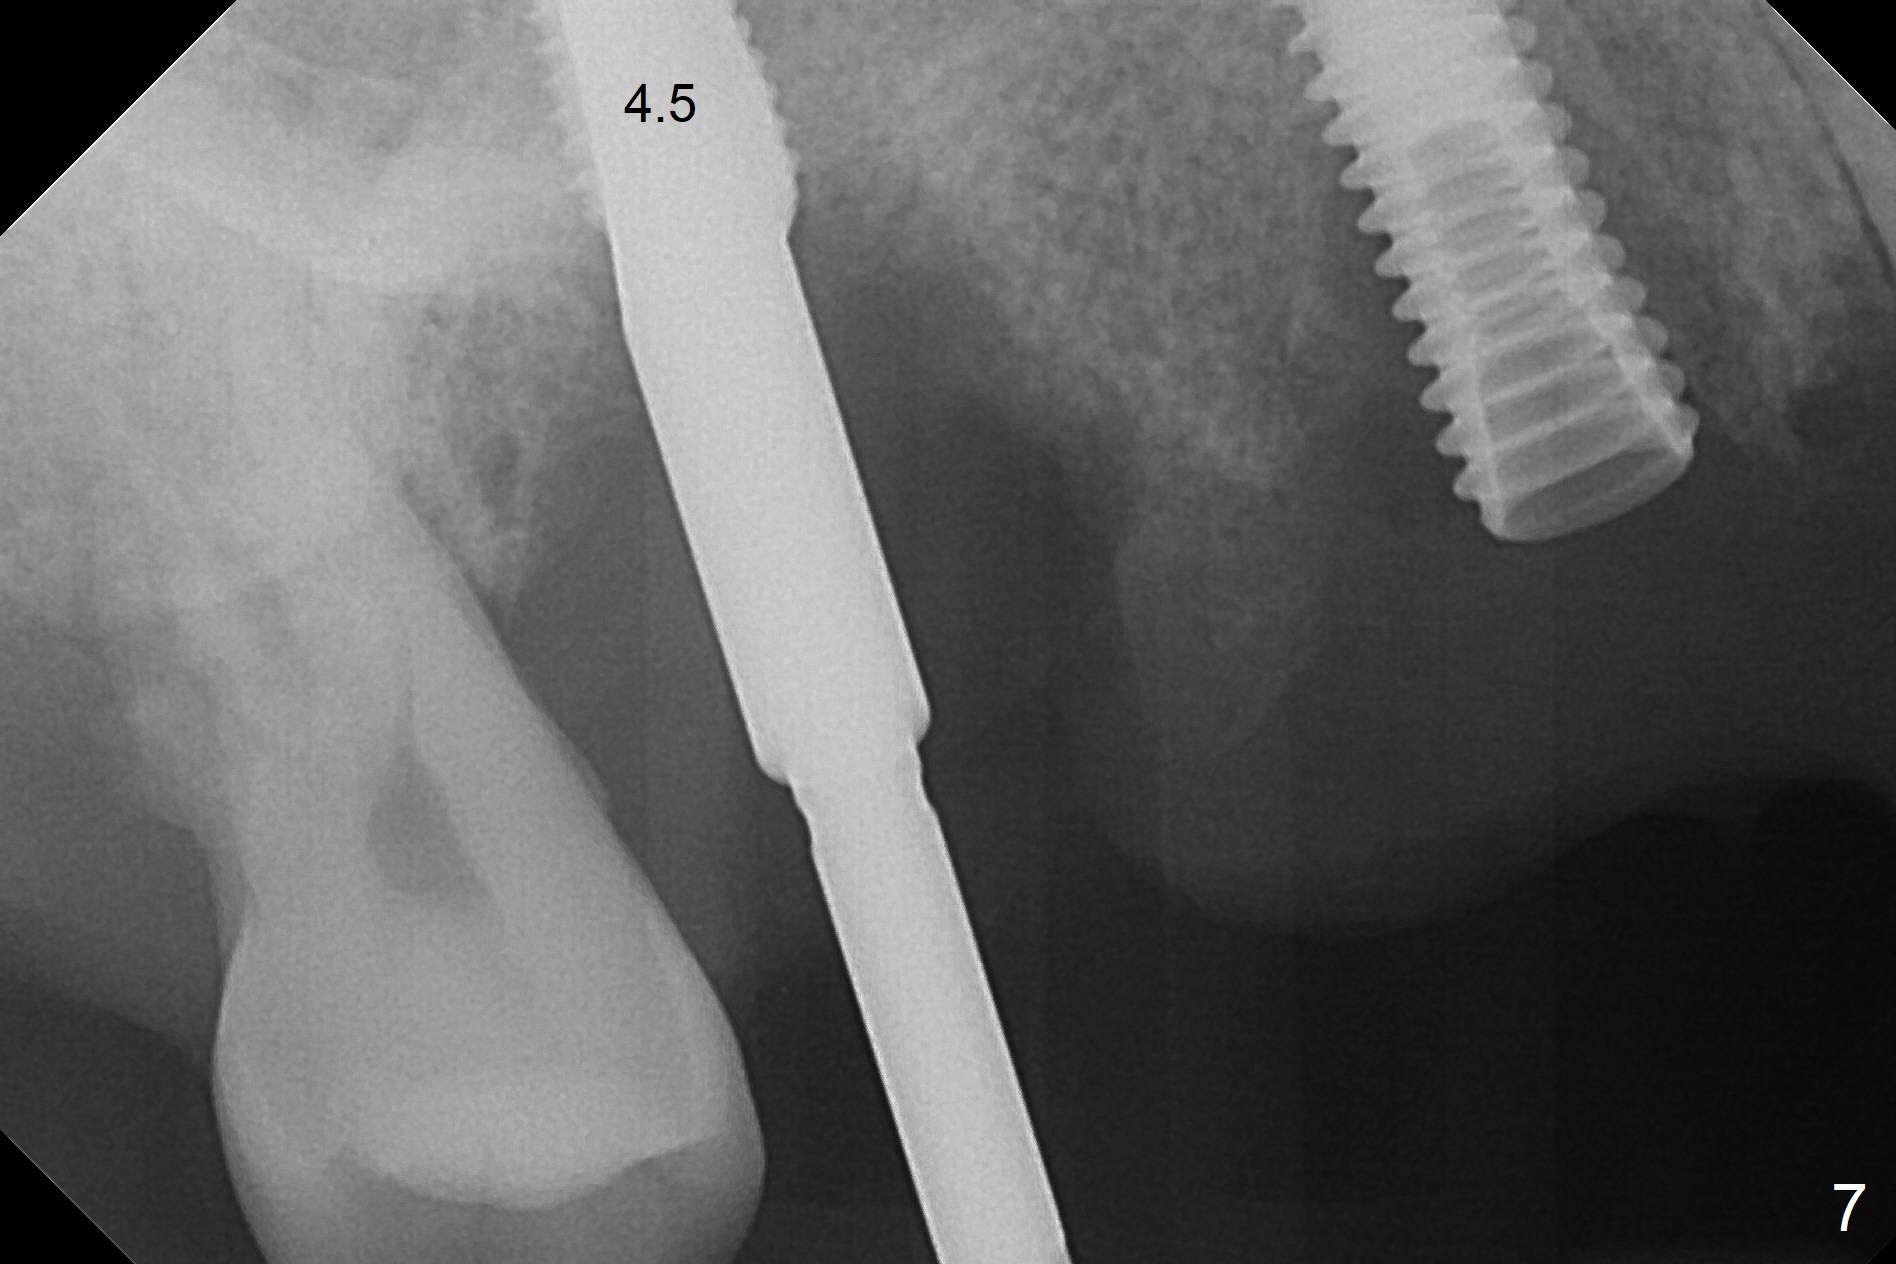

The 36-year-old man (ex-smoker, quit for 4-5 years) insists upon #3 and 5 extraction first for implants, in spite of more severe infection at #7, 14,19,30 (Fig.1-4). The gingiva around #23-26 implants is healthy 3 weeks postop (Fig.5). The initial depths at #3 and 5 are 8.5 mm (bone-level) and 18 mmm (gingiva-level (13 mm (implant length) + 5 mm cuff), respectively. When a drill penetrates the sinus floor, confirm the depth. After use of 3.8 mm drill, 4.5 mm tap drill is inserted at #3 without stability, while a 4.5x13 mm implant is placed at #5 with primary stability (Fig.6,7). Then a 5x11.5 mm is placed at #3 subcrestal proximally after sinus lift with Vanilla graft (without sinus membrane perforation; Fig.8). The implant at #5 is seated ~1 mm deeper (subcrestal mesially (^^); supracrestal distally (^)); allograft is placed around the implants prior to insertion of 6.5x7(5) and 5.5x4(5) mm abutments; last more allograft is added (Fig.9 *, 10). The implants seem to have been osteointegrated 4.5 months postop (Fig.11,12). The gingiva is healthy around the implants without bone loss 3 months post cementation (Fig.13,14).